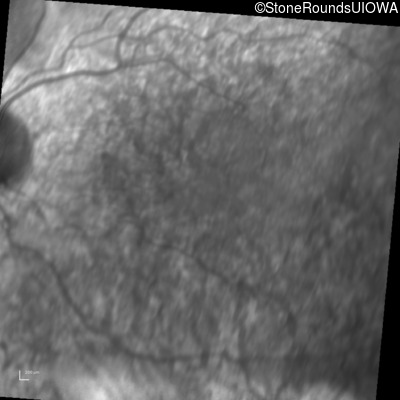

Infrared Fundus Photograph - Left - 20/32

Exemplar